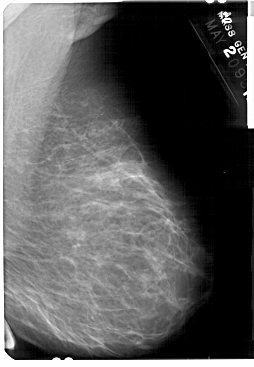

A_1369_1.LEFT_MLO

LEFT_MLO LINES 5491 PIXELS_PER_LINE 3781 BITS_PER_PIXEL 12 RESOLUTION 43.5 OVERLAY